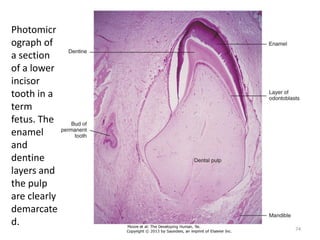

Photomicr

ograph of

a section

of a lower

incisor

tooth in a

term

fetus. The

enamel

and

dentine

layers and

the pulp

are clearly

demarcate

d.

74